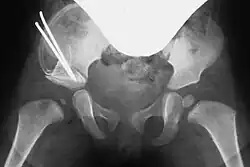

Acetabuloplastik, Schritt 4, ggf. Osteosynthese mit einem Kirschner-Draht

Entsprechend dem so entstandenen Spalt wird bei beiden Vorgehensweisen ein passender Knochenkeil (Spenderknochen/Knochenbank, siehe unten) zurechtgesägt und unter Röntgenkontrolle in den Spalt eingestößelt. Der Keil kann wenn nötig mit einem Osteosynthese-Draht (auch Kirschner-Draht genannt) fixiert werden. Bei einem geübten Operateur dauert diese Operation in etwa fünfundvierzig bis sechzig Minuten.[1][8]